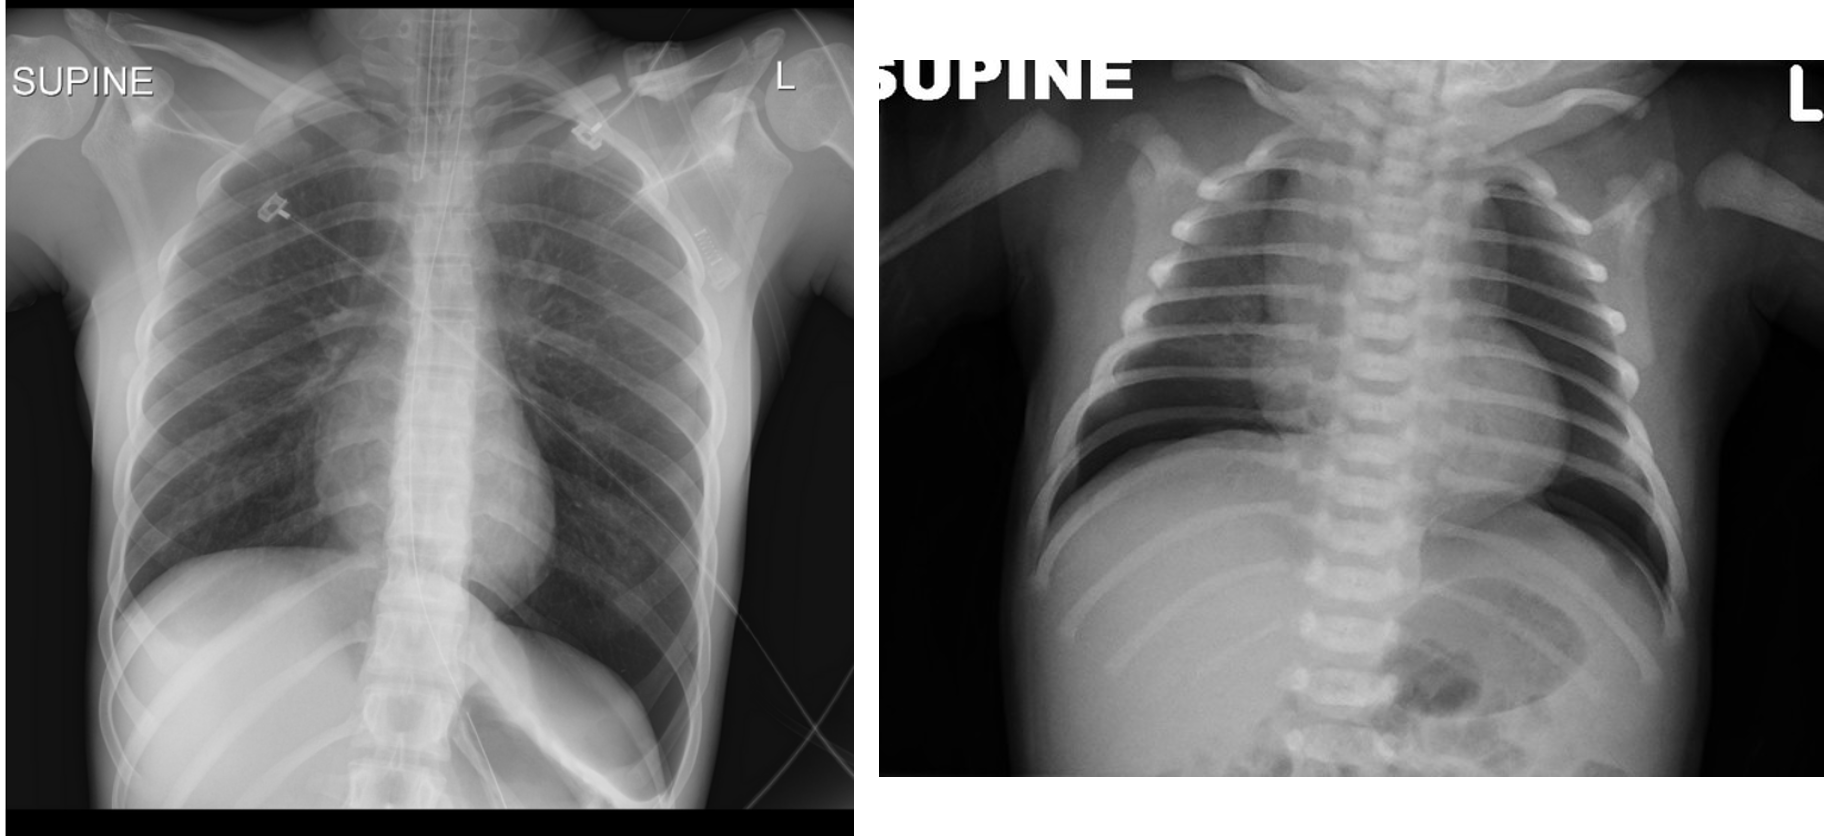

if light goes throughout lung theres pneumothoraxm if localized, its not pneumothorax.

High-intensity fiber optic light demonstrating increased transillumination on the left half of the chest suggestive of left-side pneumothorax compared to the normal right chest.

Deep Sulcus Line

- Notice:

“Deep sulcus line” indicating pneumothorax.

Continuous Diaphragm Sign

- Description:

The blue arrow points to the “continuous diaphragm sign.” The entire diaphragm is visualized from one side to the other because air in the mediastinum outlines the central portion, which is usually obscured by the heart and mediastinal soft tissue structures that are in contact with the diaphragm. The red arrow points to the air beneath and posterior to the heart. Pneumomediastinum elevating the thymus causing the “spinnaker sail” sign. Notice also the “continuous diaphragm line.”